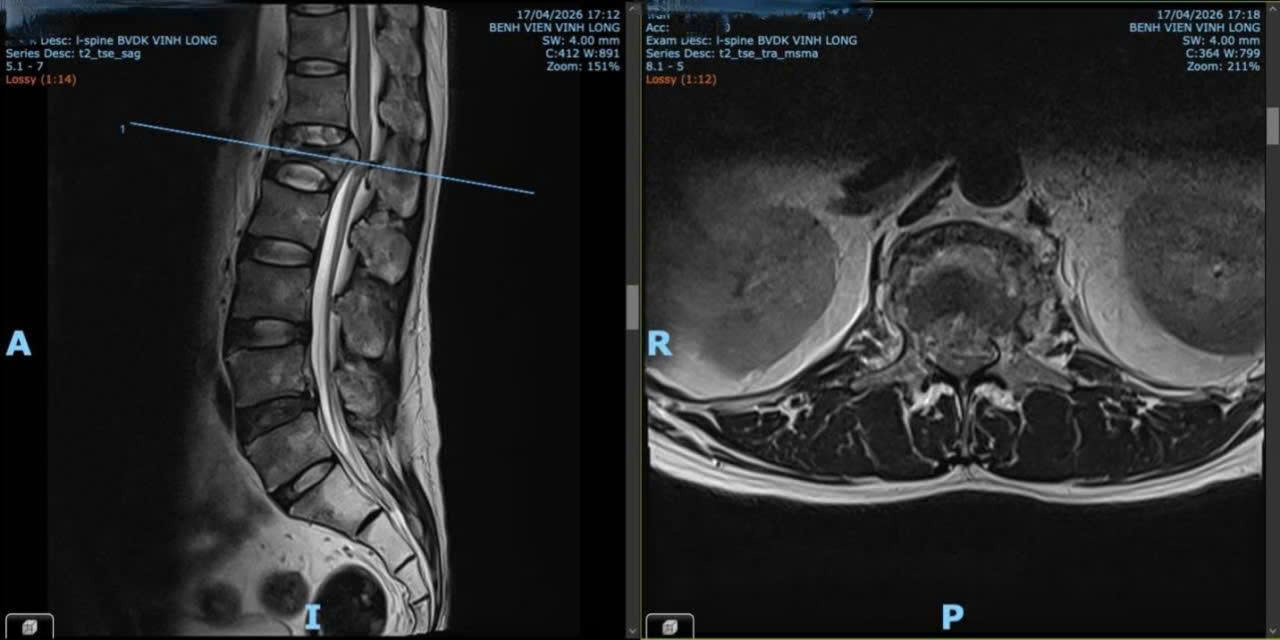

Kết quả chụp MRI cột sống thắt lưng ghi nhận xẹp đốt sống L1, mảnh gãy phía sau thân sống di lệch ra sau chèn ép bao màng cứng, gây hẹp nặng ống sống với đường kính trước sau chỉ còn khoảng 6 mm. Đồng thời, X-quang khung chậu thẳng và CT vùng hông đùi trái ghi nhận hình ảnh theo dõi hoại tử chỏm xương đùi trái.

Hình ảnh chụp X-quang cột sống trước phẫu thuật của người bệnh